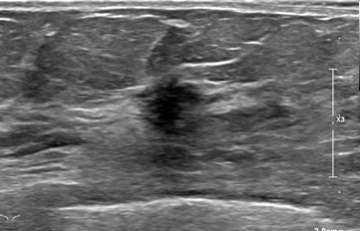

- Ultrasound (US):

Ultrasound has a higher sensitivity for detecting ILC than mammography, reported at 68-98%. A hypoechoic irregular mass with posterior shadowing is the most common imaging finding on US (60%)1. Less common findings are irregular shape and angular margins, or posterior shadowing without a discrete mass. About 10% of the time, ILC is not detected on ultrasound1.

Case 1: